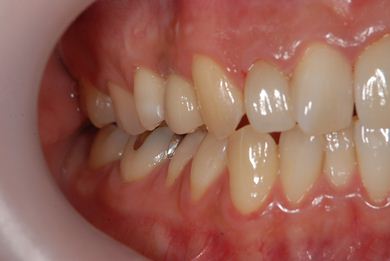

インプラントの症例写真 IMPLANT

インプラント治療+セラミック治療

| 治療内容 | インプラント1本、メタルボンドセラミッククラウン1本、オールセラミッククラウン2本(オールセラミック用土台2本) | ||||||||||||||||||||||||||||||||

| 治療期間 | 1年6ヶ月 |